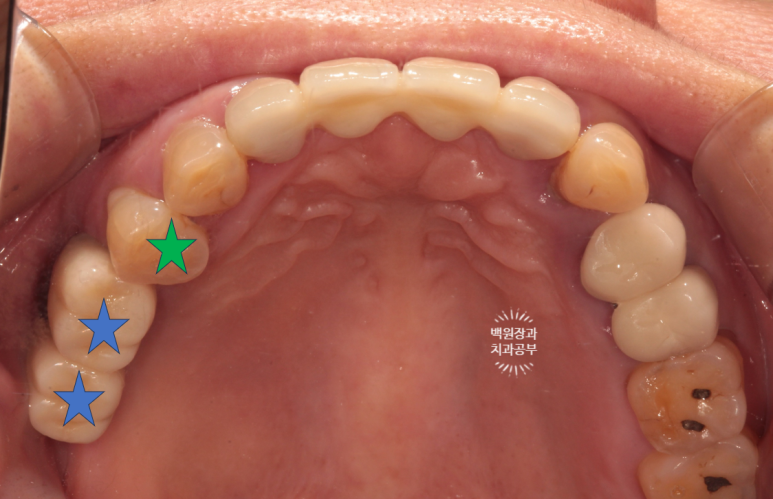

그런게 기가막힌건 그냥 입 안 사진을 봐서는 그렇게 안좋아보이지 않는다는 것입니다..

그래서 임플란트 주위염.. 임플란트 풍치는 방치되는 경향이 있습니다.

그러다 어느날 갑자기 빠진 임플란트를 들고오시죠.. 그 땐 이미 너무 늦습니다..ㅠㅠ